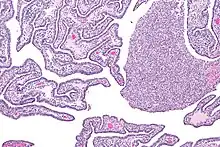

| Micrograph of acute and chronic salpingitis. H&E stain. | |

Salpingitis can be acute, chronic, or subclinical.[4]